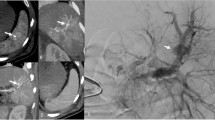

INJECTION of radiopaque media either directly into the spleen of the rat or retrogradely into tributaries of the portal venous system, followed by radiography, demonstrates the presence of distinct vascular compartments in the spleen and clarifies certain features of their venous drainage.